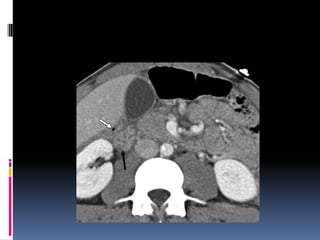

INJURIA PANCREÁTICA

 Resulta de la compresión de la glándula

contra la columna vertebral

 Manubrio de bicicleta

 Clínica y laboratorio inicialmente

inespecíficos

 Signos indirectos de lesión traumática

 Agrandamiento difuso

 Grasa peripancreática “sucia”

 Líquido periglandular

 Engrosamiento fascia pararrenal

anterior

INJURIA PANCREÁTICA  Resultade la compresión de la glándula contra la columna vertebral  Manubrio de bicicleta  Clínica y laboratorio inicialmente inespecíficos

 Signos indirectosde lesión traumática  Agrandamiento difuso  Grasa peripancreática “sucia”  Líquido periglandular  Engrosamiento fascia pararrenal anterior